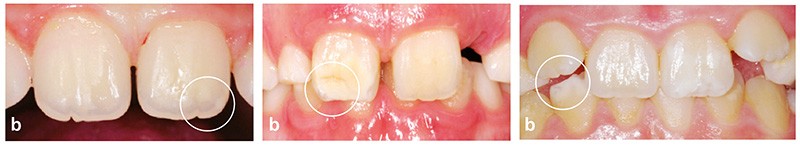

Comment la diagnostiquer ?

(fig. 1a à e)

• La MIH est une anomalie qualitative de l’émail.

• Elle touche au moins une première molaire permanente (PMP).

• Elle peut atteindre les incisives permanentes si une PMP est déjà atteinte.

• Les opacités sont bien délimitées, d’une couleur allant du blanc crémeux au jaune-brun au niveau des deux tiers

occlusaux ou des bords libres.

• Des fractures post-éruptives sont possibles.

• Il y a une étiologie multifactorielle inconnue.